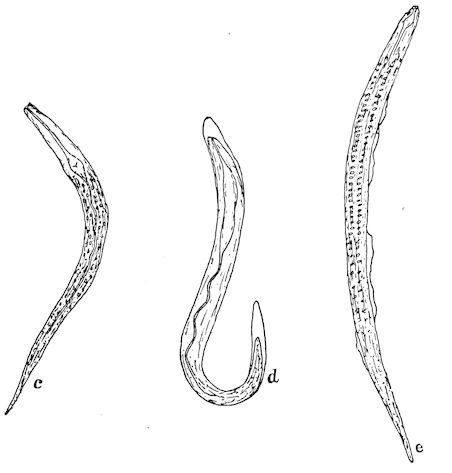

| VIII. | PARASITES OF THE DIGESTIVE APPARATUS | 263 | ||

| Gastro-intestinal strongylosis in sheep | 263 | |||

| Lumbricosis of calves | 267 | |||

| xi | Strongylosis of the abomasum in the ox | 268 | ||

| Parasitic gastro-enteritis, diarrhœa, and anæmia in cattle, sheep and lambs | 268 | |||

| Intestinal coccidiosis of calves and lambs (Psorospermosis, hæmorrhagic enteritis, bloody flux, dysentery, etc.) | 271 | |||

| Intestinal helminthiasis in ruminants | 275 | |||